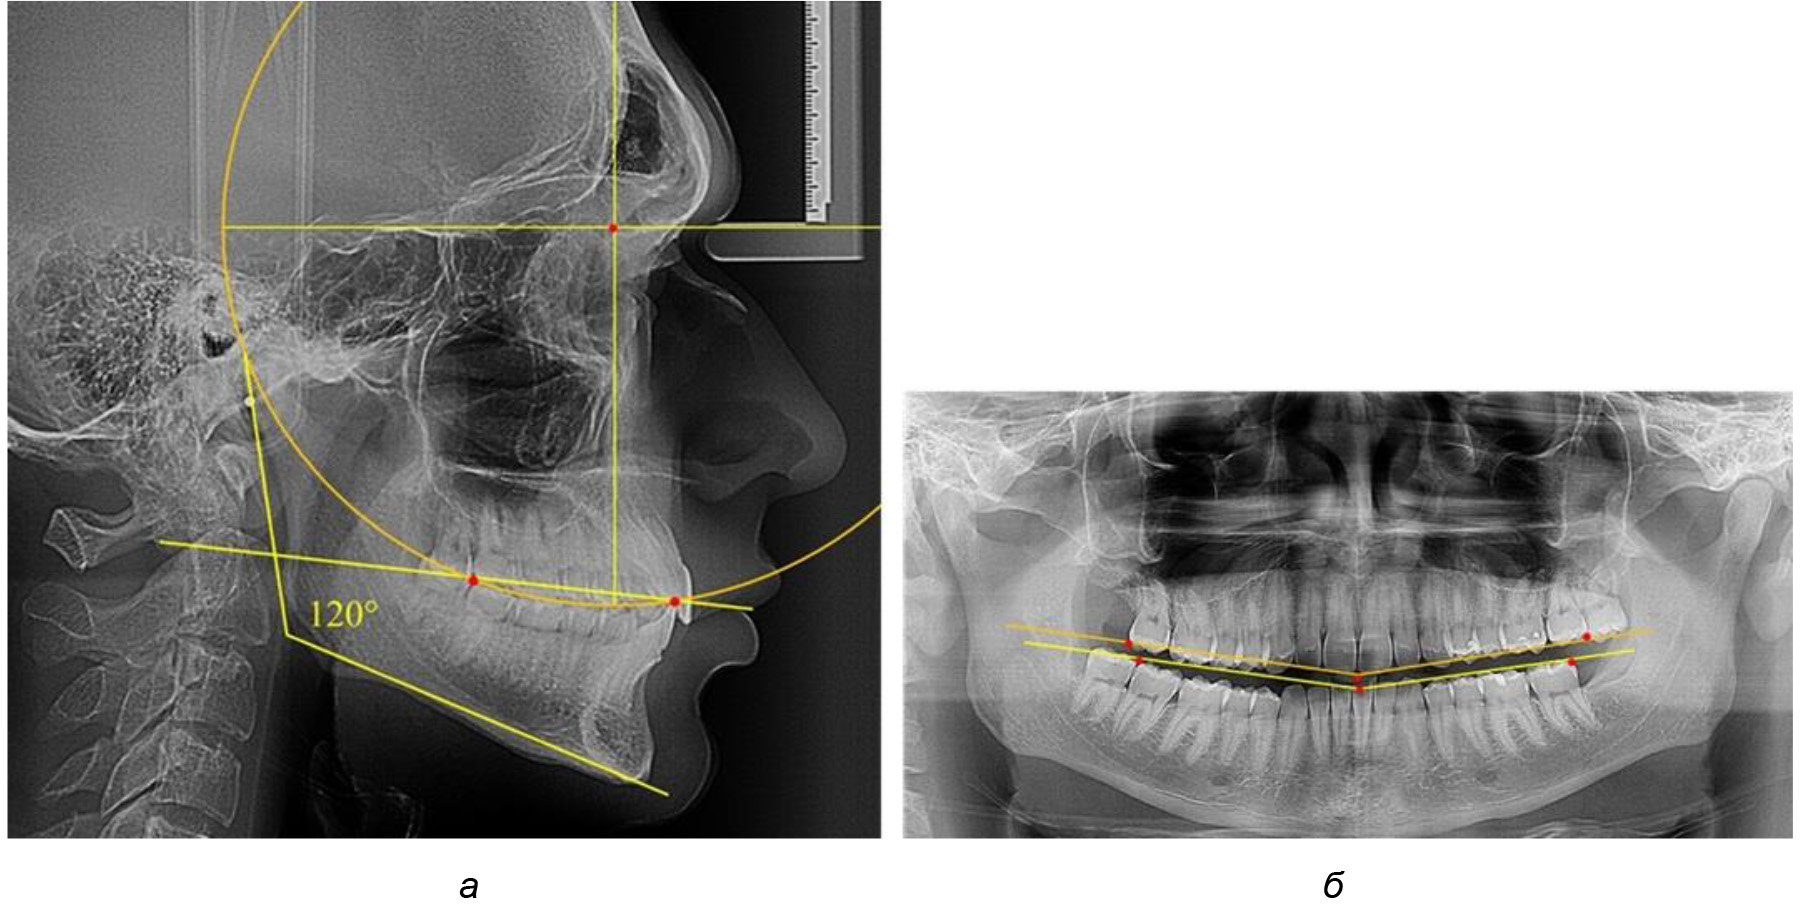

На рентгенограммах людей 2-й подгруппы (30 человек с нейтральным типом роста) величина угла нижней челюсти в среднем составила (120,34 ± 2,19) ° и характеризовала нейтральный тип нижней челюсти.

Глубина кривой Spee в среднем по 2-й подгруппе составил (3,54 ± 0,58) мм, что было незначительно меньше, чем при анализе аналогичного показателя 1-й подгруппы.

Достоверных различий с показателями, полученными при анализе ТРГ и ОПТГ, нами не отмечено (р ˃ 0,05). Деление величины радиуса круга к длине окклюзионной линии составило 1,612 ± 0,02, что, так же как и в 1-й подгруппе, было близким по значению к числу Фибоначчи (1, 618).

В 3-ю подгруппу вошли ТРГ и ОПТГ 14 человек 1-й группы, что составило (22,58 ± 5,31) % от общего количества людей 1-й группы. Величина угла нижней челюсти в среднем составила (114,85 ± 2,87)° и характеризовала горизонтальный тип нижней челюсти.

Глубина кривой Spee в среднем по 2-й подгруппе составил (2,94 ± 0,47) мм, что было меньше, чем в других подгруппах. Деление величины радиуса круга к длине окклюзионной линии составило 1,616 ± 0,02 (рис. 4).

Рис. 3. Особенности кривой Spee на ТРГ (а) и ОПТГ (б) при нейтральном типе роста нижней челюсти

Рис. 4. Особенности кривой Spee на ТРГ (а) и ОПТГ (б) у людей с горизонтальным типом лица